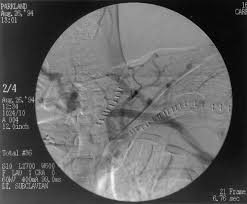

A comparative evaluation of polytetrafluoroethylene umbilical vein and saphenous vein bypass grafts for femoral-popliteal above-knee revascularization. Graft occlusion is commonly the result of stenosis at the anastomosic sites. It was applied to a series of 16 leg bypass patients to dissect totally endoscopically the greater saphenous vein for either translocated or in situ procedures. These results are comparable to or better than those reported for autogenous vein shunts created by removal and reversal of the. The first image demonstrates the stump of an occluded right femoropopliteal artery bypass graft. In the current endovascular era the femoral-popliteal bypass remains one of the most common open vascular operations. The precise role of thrombolysis in the treatment of bypass graft thrombosis is somewhat controversial.